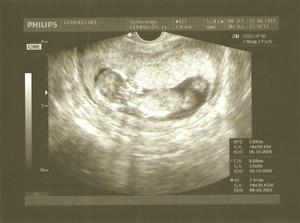

15.3.2010 - ďalšie poradňa....taaakže poradňu máme za sebou...vyčakala som sa na doktorku hodinu a pol lebo musela ísť spraviť nejaké zákroky...potom ked prišla sme pozerali bábätko a bolo to niečo nádherné....prvýkrát som videla ako sa malé pohlo, bol to super zážitok...pohlavie sme sa síce nedozvedeli, ale nevadí, hádam nabudúce....